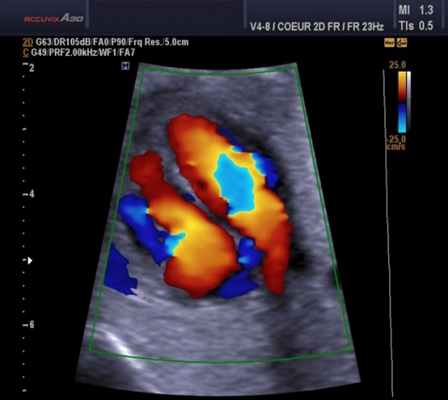

Цветовой допплер (Color Doppler). Цветовой допплер - аналог импульсного допплера, где направление и скорость кровотока картируется различным цветом. Так кровоток к датчику принято картировать красным цветом, от датчика - синим цветом. Турбулентный кровоток картируется сине-зелено-желтым цветом.